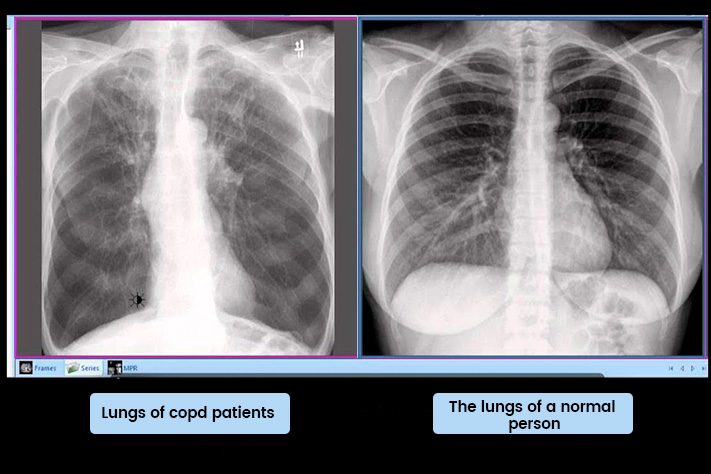

What they found: In every single patient's airways, there was a dense layer of mucus at the very bottom-below the fresh mucus, below where any treatment could reach.

The layer had been there for months. Sometimes over a year.

The cilia-those tiny hairs that sweep mucus out-were completely buried under it. Non-functional.

The molecular structure was different. Denser. Surface treatments couldn't break it down.

"Because most doctors don't know to look for it. We can't see it on X-rays. We keep prescribing treatments that only work on the surface."